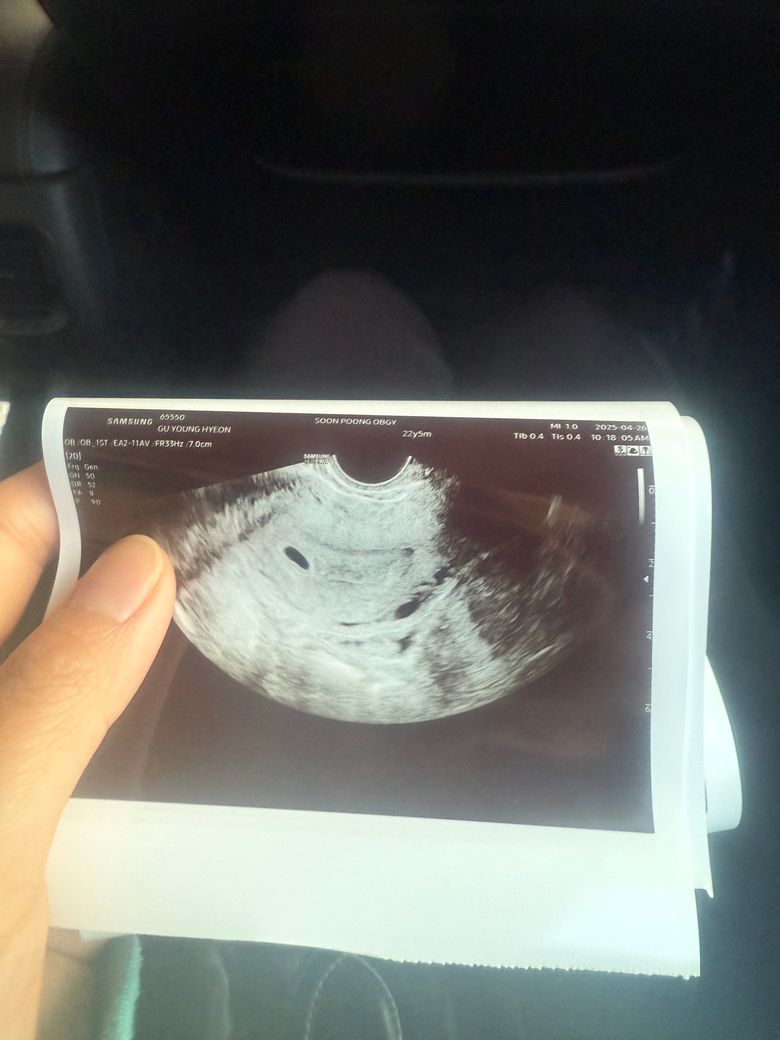

아기집 한개인거 맞죠???? 초음파 사진을 보니 동그란 구멍이 두개 있는것같아서요!!!!!!!!!!!!!!!!!’

한개 맞겠죠?

• 1번 째 사진

하나가 보이긴 하는데 그 아래 구조물 관련 자세한 초음파 해석은 담당 산부인과 전문의와 하시는게 가장 정확하고 안전합니다

담당의가 아기집이 한개라고 했으면 단태아가 맞을 것이고 의문이 남는다면 다음 방문에서 상의 해 보시기 바랍니다